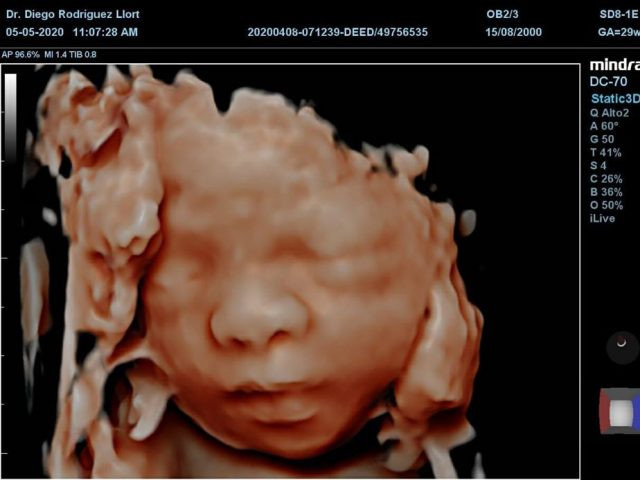

• Ultrasonido 3D y 4D: Las ecografías en tres dimensiones y cuatro dimensiones permiten ver de forma más clara al bebé, otorgándole volumen y movilidad en el 4D.

• Ultrasonido 5D: La ecografía 5D es capaz de realizar una reconstrucción más definida y realista del feto. La nueva generación de ecógrafos de alta resolución incrementa de manera decisiva la capacidad diagnóstica y la detección de malformaciones fetales.